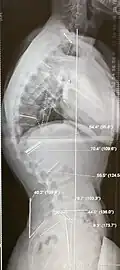

Für eine sorgfältige Diagnose bei Scheuermannscher Krankheit ist eine seitliche Ganzwirbelsäulenaufnahme erforderlich, bei der der Kyphose- und Lordosewinkel nach COBB vermessen wird. Bei der über die Norm hinausgehenden Kyphose der Brustwirbelsäule kommt es kompensatorisch zu einer Hyperlordose der Lendenwirbelsäule, der klinische Befund zeigt hier eine Hohlkreuzposition. Auch die betroffenen Keilwirbel sollen benannt und in ihrem Keilwinkel vermessen werden. Wirbelkörper mit Normabweichungen sollten benannt und beschrieben werden (z. B. „Schmorlscher Knoten, 7 mm Durchmesser, in Deckplatte WK Th 5 Keilung 15°, ventrale Randeinbrüche“). Die Fixierung oder Restbeweglichkeit der Wirbelsäule ist durch eine Vermessung nach Schober und Ott zu dokumentieren. Die Aufrichtung der Kyphose in Rutschhalte und tiefer Rutschhalte sind Anhaltswerte für die konservativ erreichbaren Therapieergebnisse. Ohne sorgfältige Diagnose und Dokumentation der Messwerte ist die Beobachtung und Prognostik der Progredienz (Verschlechterungstendenz) nicht möglich.

Korsette und Orthesen sind auf alle Fälle dann therapeutisch wirksam, wenn sie mindestens 40 % des Cobb-Winkels korrigieren, der über die Normvariante als Fehlstatik der Wirbelsäule hinausgeht:

Beispiel:

- Normvariante BWS-Kyphosewinkel 15 bis 25 Jahre etwa 30° Cobb

- Patient ohne Korsett: 70° Cobb.

- Patient im Korsett: 50° Cobb. = 50 % Korrektur

- Patient im Korsett: 30° Cobb = 100 % Korrektur

- Patient im Korsett: 20° Cobb = 10° Überkorrektur